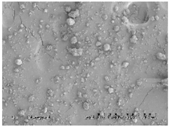

When considering the marked difference in dissolution profiles of the same composition (25% drug load (DL) HPMCAS-MF spray-dried dispersion versus 25% DL HPMCAS-MF HME dispersion), it is important to note the different properties of the spray-dried granules versus the hot melt granules, such as density, particle size, and surface area. These properties can drastically impact the dissolution profile. As shown in Table 3, the HME particles were significantly larger than the SDD granules, resulting in a much smaller surface-area-to-drug-content ratio, and the different drug release profiles of the two dispersions could be attributed to this difference. To gain a better understanding of the impact of particle size on dissolution, the HME particles were milled to different sizes using different milling techniques, and the dissolution profile in SGF was compared to that of the SDD (Figure 4). The rank order of dissolution matched the particle size of each dispersion (spray-dried particles being the smallest, and Fitz-milled HME the largest), indicating that surface area plays an important role in dissolution of the solid dispersions. Since the cryo-milled HME and the spray-dried dispersion have particle size in the same range, comparable dissolution profiles were obtained in the SGF stage for both solid dispersions.

Table 3.

Morphology and particle size of 25% DL HPMCAS-MF solid dispersions at 150× magnification.